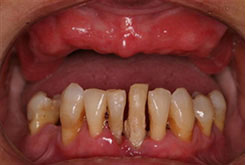

骨量严重萎缩的情况下,利用斜行植体等技术,避免植骨手术。

可以解决全口、半口无牙颌、 牙槽骨严重萎缩/极薄问题。